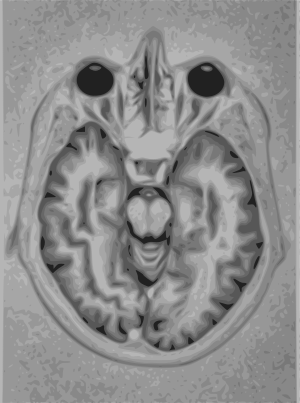

تمثيل للتصوير بالرنين المغناطيسي MRI للمخ

التصوير بالرنين المغناطيسي يستخدم مغناطيسات قوية ليستقطب نواة الهيدروجين (بروتون وحيد) في جزيئات الماء الموجودة في الأنسجة البشرية مولدة إشارة قابلة للالتقاط حيث يتم فك تشفيرها معطية صورة للجسم. يستخدم التصوير بالرنين المغناطيسي ثلاث أنواع من الحقل الكهرومغناطيسي: حقل مغناطيسي ساكن قوي جداً (من فئة عدة واحدات تسلا) من أجل استقطاب نويات الهيدروجين، يدعى بالحقل الساكن، هناك حقل أضعف منه متغير مع الزمن (من فئة 1 كيلو هرتز) من أجل الترميز الخاص، يسمى بحقل الميلان، وحقل موجات راديوية ضعيف من أجل التلاعب بنويات الهيدروجين لإنتاج إشارات ممكنة القياس يتم تجميعها خلال هوائي الموجات الراديوية. كما في الأشعة المقطعية فإن التصوير بالرنين المغناطيسي انتج صوراً للمقاطع والشرائح الرقيقة للجسم ولذلك تم اعتباره نوعاً من أنواع التصوير بالأشعة المقطعية. تتمكن أجهزة التصوير بالرنين المغناطيسي الحديثة من إنتاج صوراً ثلاثية الأبعاد والتي تعتبر تعميماً للصور الثنائية البعد. على خلاف التصوير بالأشعة السينية فإن التصوير بالرنين المغناطيسي لا يستخدم أي نوع من الأشعة المؤينة وبالتالي فإنه لا يتصاحب مع مخاطر صحية، حيث أنه ليس من المعروف وجود أي مخاطر صحية على المستوى البعيد للتعرض إلى حقل مغناطيسي ساكن قوي ولكن هذا الأمر لا يزال موضع جدال وبحث علمي. ولذلك لا يوجد أي تحديد لعدد المرات التي من الممكن للمريض أن يتعرض لها للتصوير بالرنين المغناطيسي على خلاف التصوير بالأشعة السينية. ولكن يوجد مخاطر صحية من جراء تسخين الأنسجة بتعريضها لحقل الأمواج الراديوية والتأثير على الأجهزة المزروعة ضمن الجسم كمنظمات عمل القلب. على اعتبار أن طريقتي التصوير بالأشعة المقطعية والتصوير بالرنين المغناطيسي تختلفان في حساسيتهما لمواد الأنسجة المختلفة، لذلك فإن الصور الناتجة عن كلا الطريقتين تختلف بشكل ملحوظ. تنتج الصور في الأشعة السينية المقطعية عن طريق حجب مرور الأشعة بواسطة الأنسجة الكثيفة، بينما تكون جودة الصورة ضعيفة في مناطق الأنسجة الطرية. بينما بروتون الهيدروجين يكون موجوداً في معظم الأنسجة الطرية التي تحتوي على الكثير من جزيئات الماء. وهنا تستخدم تقنية مطابقة الصور بواسطة الكمبيوتر للحصول على صورة واضحة لمختلف الأنسجة بمطابقة صورتي الأشعة السينية والرنين المغناطيسي.